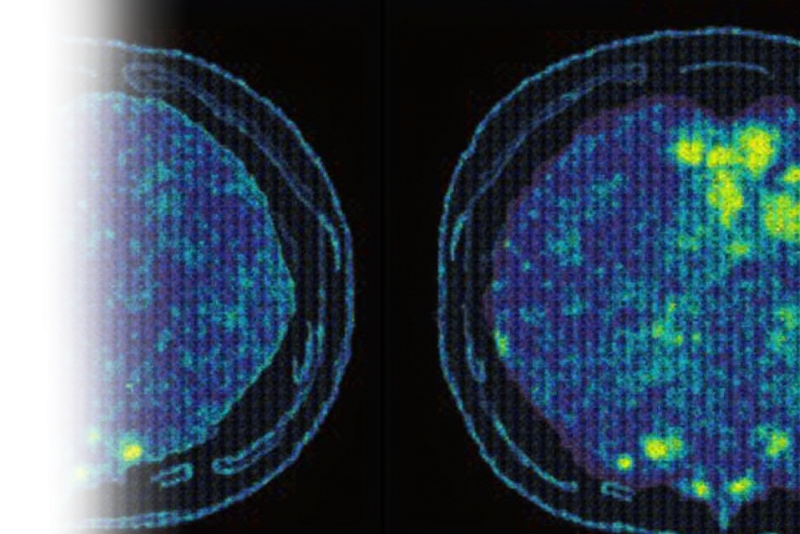

Компьютерная томография мягких тканей с контрастированием – важный метод исследования состояния мягких тканей с внутривенным ведением йодсодержащего контрастного препарата.

КТ мягких тканей с контрастированием является более информативным методом диагностики, в сравнении с нативным (без введения контраста) исследованием ввиду большей контрастности тканей, что позволяет более точно определить состояние мягких тканей и выявить патологии.

Также данный метод позволяет ввести контрастный препарат в структуру гематомы для подтверждения или опровержения наличия продолжающегося кровотечения и поиска его источника.